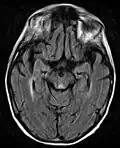

Axial MRI B=1000 DWI image showing hyperintense signal indicative of restricted diffusion in the mesial dorsal thalami -

Axial MRI FLAIR image showing hyperintense signal in the periaqueductal gray matter and tectum of the dorsal midbrain